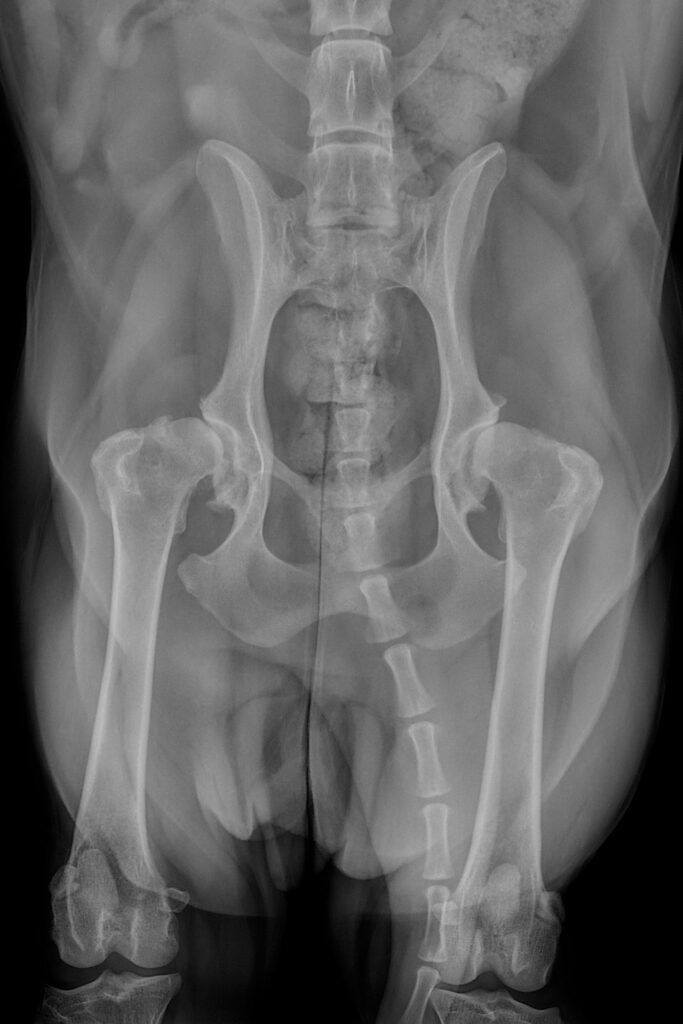

Rosey’s X-rays for her hip dysplasia

Super spaniel Rosey came in with her mum, Senior Surgical Technician Kirsty, with some ongoing lameness and stiffness on her hind limbs.

As a first step, her orthopaedic surgeon requested for some radiographs to be taken using one of our three X-ray units to better understand what was happening in Rosey’s bones and joints. X-ray images are really effective at showing bony detail and providing an overall assessment of the bone integrity and alignment.

They showed that poor Rosey was suffering from bilateral hip dysplasia and associated osteoarthritis, but fortunately, total hip replacements were a treatment option and Kirsty opted to go ahead with the procedure for her canine friend, replacing the right hip first and the left nine months later.

Postoperative radiographs were also taken immediately following surgery and at regular intervals after each operation to demonstrate good implant placement and bone healing.